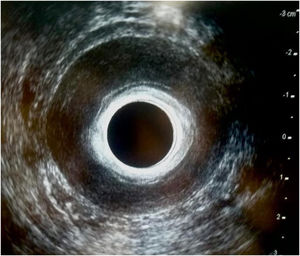

We present the case of a 53-year-old woman, whose medical history of interest only included cesarean section for the delivery of twins. She reported symptoms of proctalgia and difficulty passing stool over the past 3 years. On physical examination, she presented with pain during digital rectal examination and anal hypertonia, with no associated fissure. We performed endoanal ultrasound and requested a dynamic pelvic MRI, which showed homogeneous circumferential thickening of the IAS, in addition to tricompartmental pelvic floor descent during defecation, with no relaxation of the IAS. The patient did not improve with oral muscle relaxants, topical nifedipine, or local infiltration of botulinum toxin, and she is awaiting internal lateral sphincterotomy (Figs. 1 and 2).